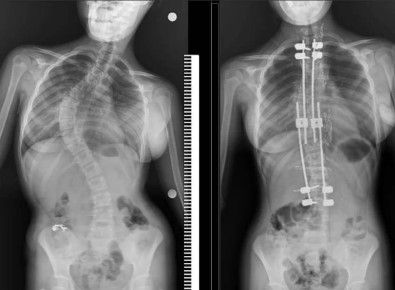

Samsun Egitim ve Arastirma Hastanesi’nde ilk defa 10 yasindaki bir çocuga skolyoz (omurga egriligi) ameliyati yapildi. Özel hastanelerde 300-500 bin TL arasinda yapilan bu ameliyat kamu hastanesinde ücret alinmadan basarili bir sekilde gerçeklestirildi.

Büyüme koruyucu sisteminin uygulandigi ameliyatta minik Zümra’nin omurgasi düzeltildi. Özel hastanelerde ortalama 300 ile 500 bin TL arasinda yapildigi ögrenilen bu ameliyat artik Samsun Egitim ve Arastirma Hastanesi’nde ücretsiz olarak gerçeklestiriliyor.

Ameliyat hakkinda bilgi veren Dr. Ömer Bozduman, "Bu gibi durumlarda uzayan rot dedigimiz bir sistem uyguluyoruz. Bunun nedeni çocuklari yasi küçük oldugu için füzyon dedigimiz kaynatma ameliyati yaparsak akcigerlerinde yetersiz gelisme, gögüs kafeslerinde yetersiz gelisme ve kanallarinda yetersiz gelisme olusabilecegi için büyüme koruyucu cerrahi yapiyoruz. Büyüme koruyucu cerrahinin diger füzyon cerrahisinden alternatifi sudur: Düzenli araliklarla düzeltme yapiyoruz. Çocuk büyüdükçe biz de bu sistem anestezi altinda ya da anestezisiz olarak uzatarak çocugun yeterli omurga büyüklügüne ulastiktan sonra yeterli kalici ameliyati gerçeklestiriyoruz. Anestezi hocamiz Doç. Dr. Serkan Turgal yardimi ile bu ameliyati basariyla gerçeklestirdik. 10 yasindaki hastamiza büyüme koruyucu sistemi yerlestirdik. Düzenli araliklarla uzatmalarini yapacagiz. Nihai ameliyatini omurgasi büyüdükten sonra gerçeklestirecegiz. Egitim ve Arastirma Hastanesi olarak bir ilki gerçeklestirdik. Hastamiz gayet iyidir. Birinci günün kalkip yürüdü. Dördün gün sonra taburcu ettik. Herhangi bir nörolojik veya baska bir sorunla karsilasmadik. Ihtiyaci olan tüm hastalarimiza Samsun Egitim ve Arastirma Hastanesi olarak devletimizin imkanlariyla bu hizmeti ücretsiz olarak veriyoruz. Aileler bu semptomlar hakkinda dikkatli olmalidir. En ufak süphede polikliniklerimize bekliyoruz. Bizler yardimci olacagiz" diye konustu.